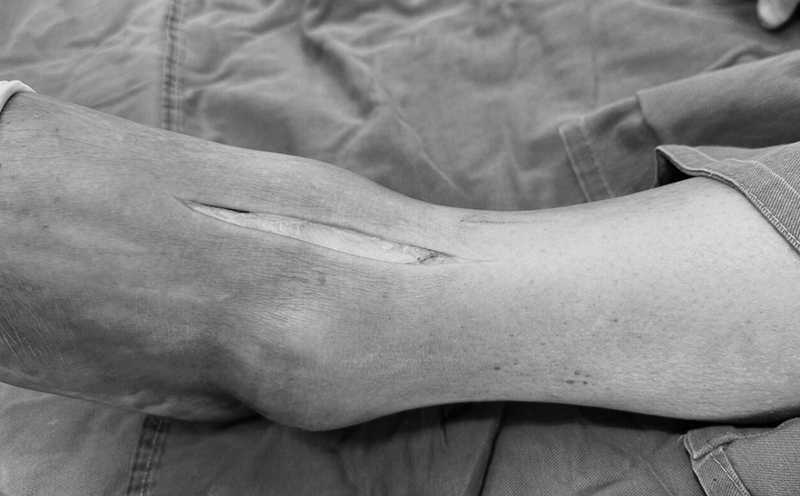

1. 平仰卧位,垫高患侧髋关节,做21.5cm切口,第一个位于胫前肌腱内侧,第二个位于第三腓骨肌腱外侧 。

微创手术切口